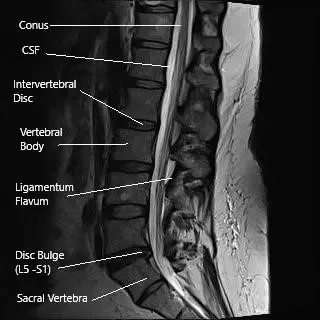

Sagittal and axial sections of the lumbar MRI